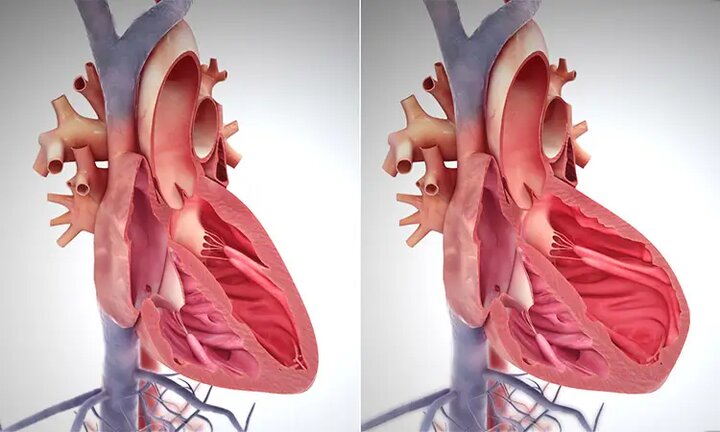

۳ عامل کشنده که قلب شما را نشانه گرفتهاند!

فوق تخصص جراحی قلب در بیمارستان رجایی گفت: بیماریهای قلبی، بهویژه گرفتگی عروق کرونر، اصلیترین عامل مرگومیر در کشور است.

اثر آلودگی هوا بر قلب؛ از نارسایی تا حملات قلبی

متخصص قلب و عروق گفت: آلودگی هوا یکی از عوامل خطرناک برای بیماران قلبی است که میتواند علائم بیماریهایی مانند فشار خون بالا، گرفتگی عروق و آریتمی قلبی را تشدید کند.

سالانه ۱۶۰ هزار مرگ قلبی در ایران رخ میدهد

رئیس و دبیران علمی و اجرایی کنگره بین المللی نارسایی قلب، ضمن توضیحاتی درباره شایع ترین عارضه های قلبی در کشور، به مسائل و چالش های حوزه قلب و عروق اشاره کردند.